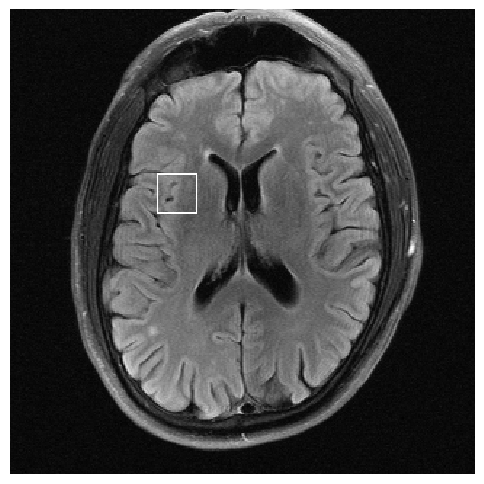

Figure 3: Reconstructions results. Rows 1 and 3: Examples of comparing the ground truth (GT) fully sampled image to the reconstructed images obtained by the three models (1-3), NPB-REC, baseline, E2E-VarNet trained with Dropout, and the NPB-REC std. map at accelerations R=4𝑅4R=4italic_R = 4, R=8𝑅8R=8italic_R = 8, respectively. Rows 2 and 4: The corresponding annotated ROIS of Nonspecific white matter lesions.

Fig. 3 presents examples of reconstruction results obtained by (1) our NPB-REC approach, (2) the baseline, and (3) Monte Carlo Dropout, for equispaced masks with two different acceleration rates R=4𝑅4R=4italic_R = 4 and R=8𝑅8R=8italic_R = 8. The reconstructed images predicted by the three models are smoother than the reference image. This is due to the fact that all the models were trained with SSIM loss, which tends to produce overly smooth reconstructions while preserving the diagnostic content and the anatomical features Sriram et al. (2020a). These images can be enhanced by dithering the image by adding a small amount of random Gaussian noise to produce a more textured reconstruction, as proposed in Sriram et al. (2020b).

Table 1 presents the mean PSNR and SSIM metrics, calculated over the whole inference set, for the three models. Our NPB-REC approach achieved significant improvements over the other methods in terms of PSNR and SSIM (Wilcoxon signed-rank test, pmuch-less-than\ll1e-4, except for SSIM values in line W, R=4𝑅4R=4italic_R = 4 where they are roughly the same for NPB-REC and Baseline). The improvement in the reconstruction performance can be noted both quantitatively from the metrics, especially for masks with acceleration rate R=8𝑅8R=8italic_R = 8, and qualitatively via the images of annotations, where our results show less smoothness than those obtained by Dropout.